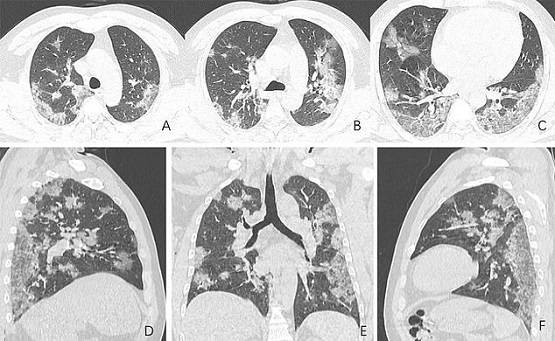

फेफड़ों की पहली पिक्चर (ए) और आखिरी पिक्चर (एफ) में आप आसानी से अंतर देख सकते हैं. सफेद रंग के ये धब्बे असल में बलगम है जो फेफड़ों में हवा की जगह भर जाता है. इसके बाद इंसान को सांस लेने में दिक्कत होने लगती है.

PHOTO: RSNA